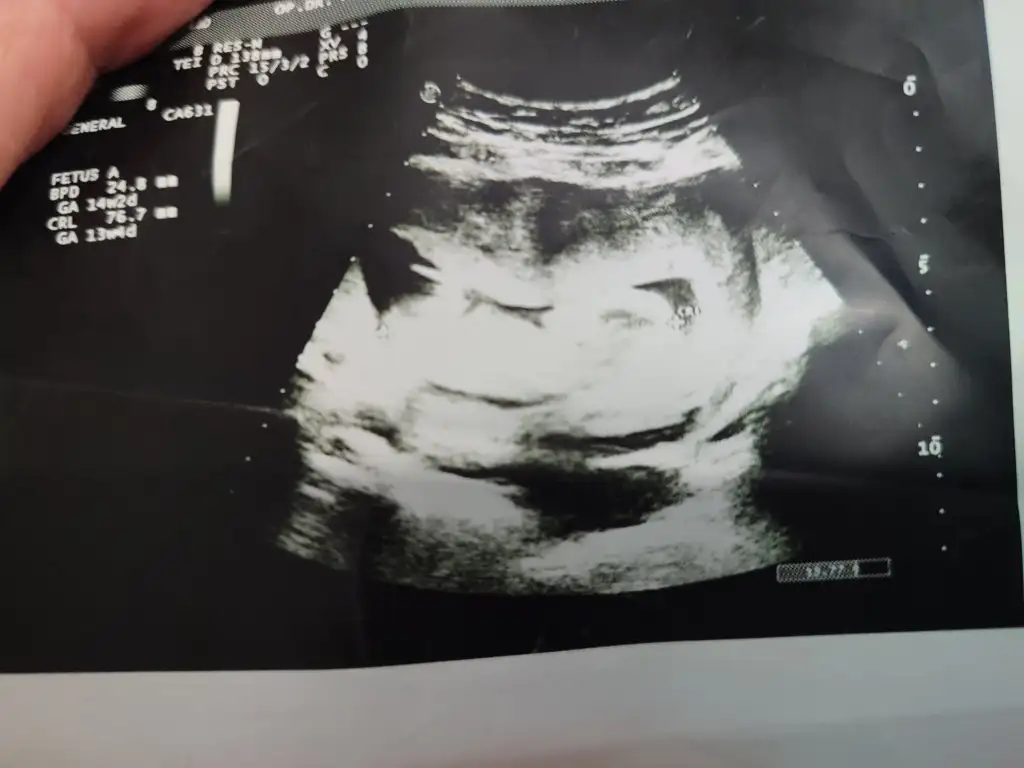

İyi günler tahmini olan varmı